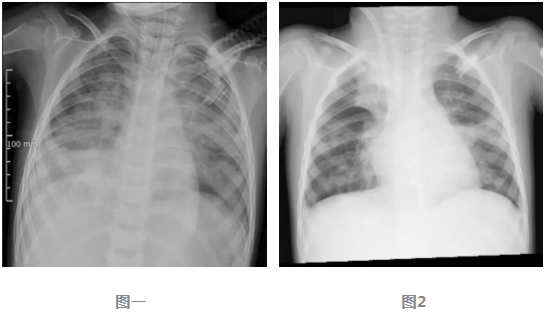

圖1 ECMO上機前,肺部結構模糊,呈現(xiàn)“白肺”影像表現(xiàn)。

圖2 ECMO支持治療5天后,肺部影像清晰度明顯改善。